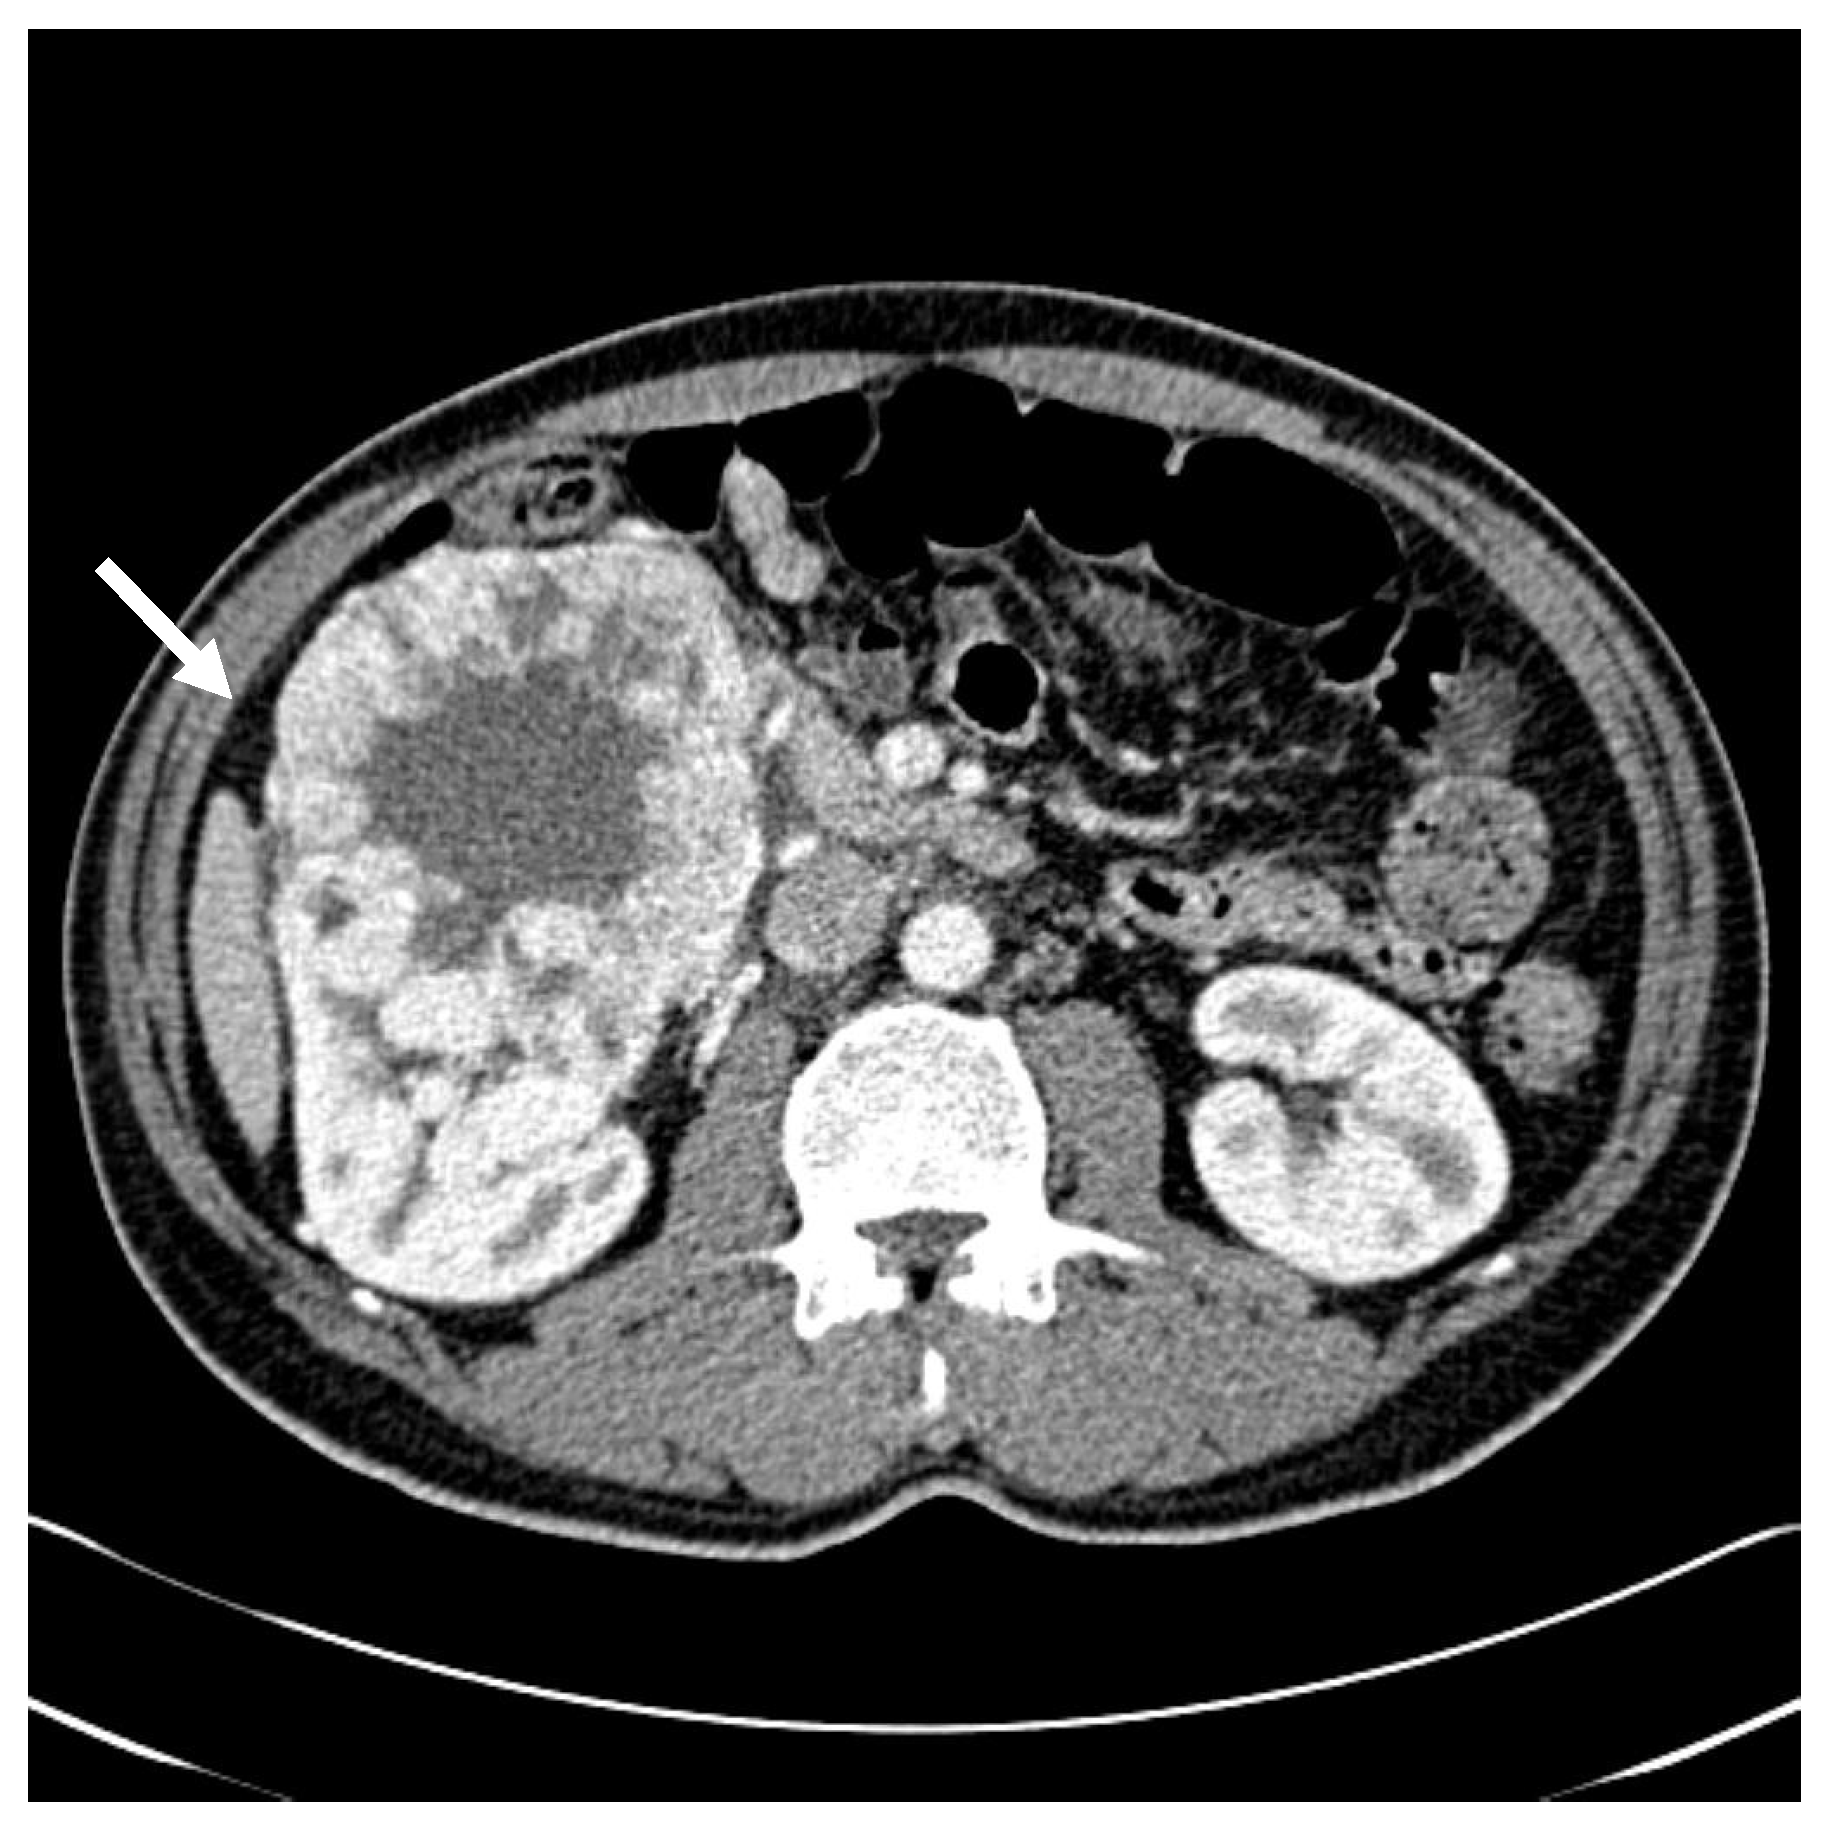

| Initial diagnosis | Initial presentation with gross hematuria Abdominal CT: 10.4 × 14.3 × 10.0 cm3 right renal mass | |

| 5.5 years after surgery | Referred due to exophthalmos → CT/MRI: Right adrenal (2.9 × 3.0 × 2.6 cm3) and right retrobulbar (3.0 × 3.7 × 2.8 cm3) metastases | |